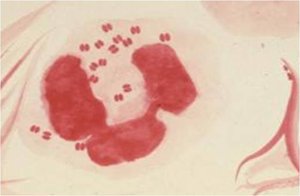

Neisseria is a genus of gram-negative cocci that typically occur in pairs (diplococci) with flattened adjacent sides. Two primary human pathogens in this genus are Neisseria gonorrhoeae and Neisseria meningitidis. These bacteria are fastidious, requiring enriched media and increased CO2 for laboratory growth.

Gram Stain | Gram-negative diplococci |